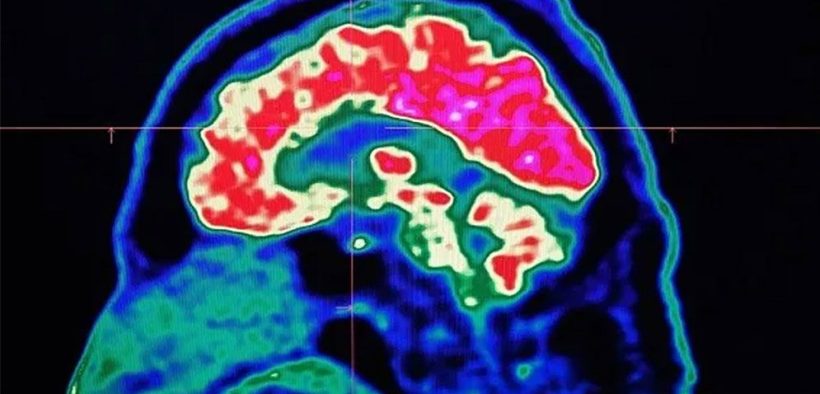

চলতি বছর কেরালায় ৬১টি সংক্রমণের ঘটনার কথা উল্লেখ করেছে কেরালার স্বাস্থ্য মন্ত্রণালয়। জানিয়েছে, ‘মস্তিষ্ক-খেকো অ্যামিবা’র কারণেই মূলত এ রোগ হয়। সাম্প্রতিক সপ্তাহগুলোতে মৃত্যুর সংখ্যা উল্লেখযোগ্যভাবে বেড়েছে। রাজ্যজুড়ে জারি করা আছে স্বাস্থ্য সর্তকতা।

‘মস্তিষ্ক-খেকো অ্যামিবা’ নেগলেরিয়া ফাওলেরি নামক জীবাণু দ্বারা ছড়ায়। এর সংক্রমণে মস্তিষ্কের টিস্যু পুরোপুরি ধ্বংস হয়ে যায়। ফলে মস্তিষ্ক মারাত্মক ফুলে যায়। এ জীবাণুর আক্রমণে আক্রান্তদের বেশিরভাগেরই মৃত্যু হয়। শিশু থেকে বৃদ্ধ- সব বয়সি মানুষের মাঝে ছড়াতে পারে এই অনুজীব।